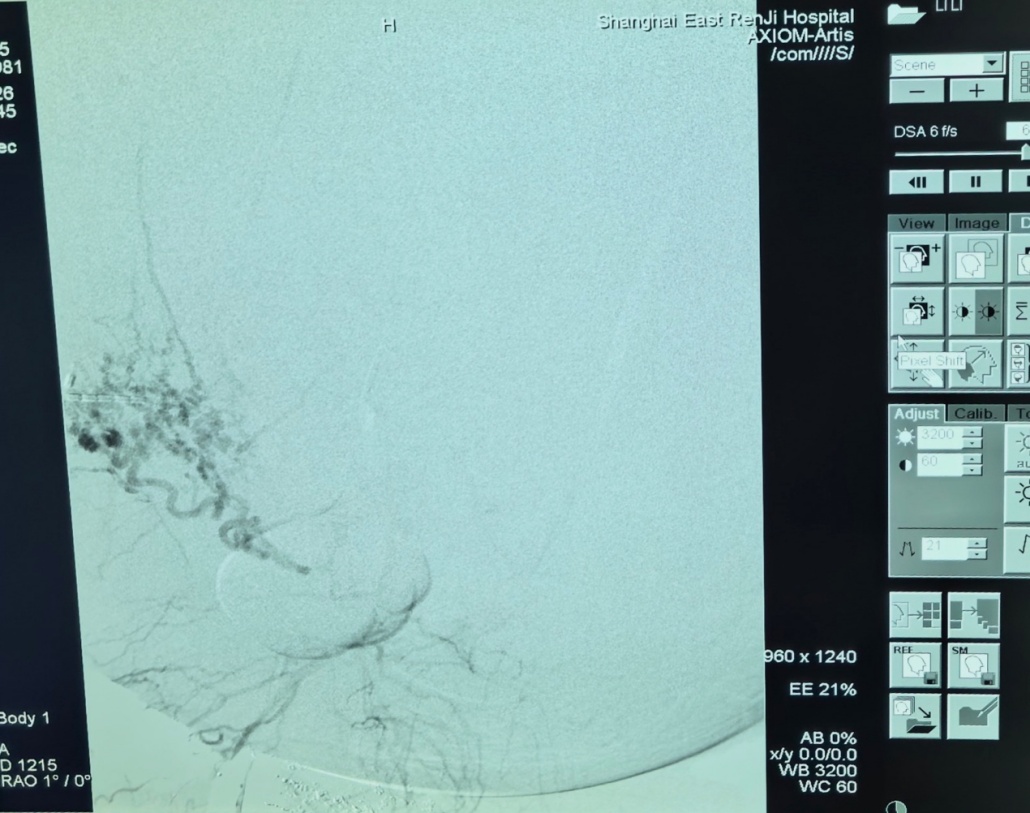

医务处牵头,妇产科、肿瘤介入科、麻醉科、泌尿科、输血科、重症医学科等多学科专家紧急会诊,共同绘制“拆弹”蓝图:先由肿瘤介入科栓塞肿瘤主要供血血管,降低大出血风险;再由妇产科团队实施肿瘤完整切除;麻醉科全程护航生命体征,输血科备足急救血源。